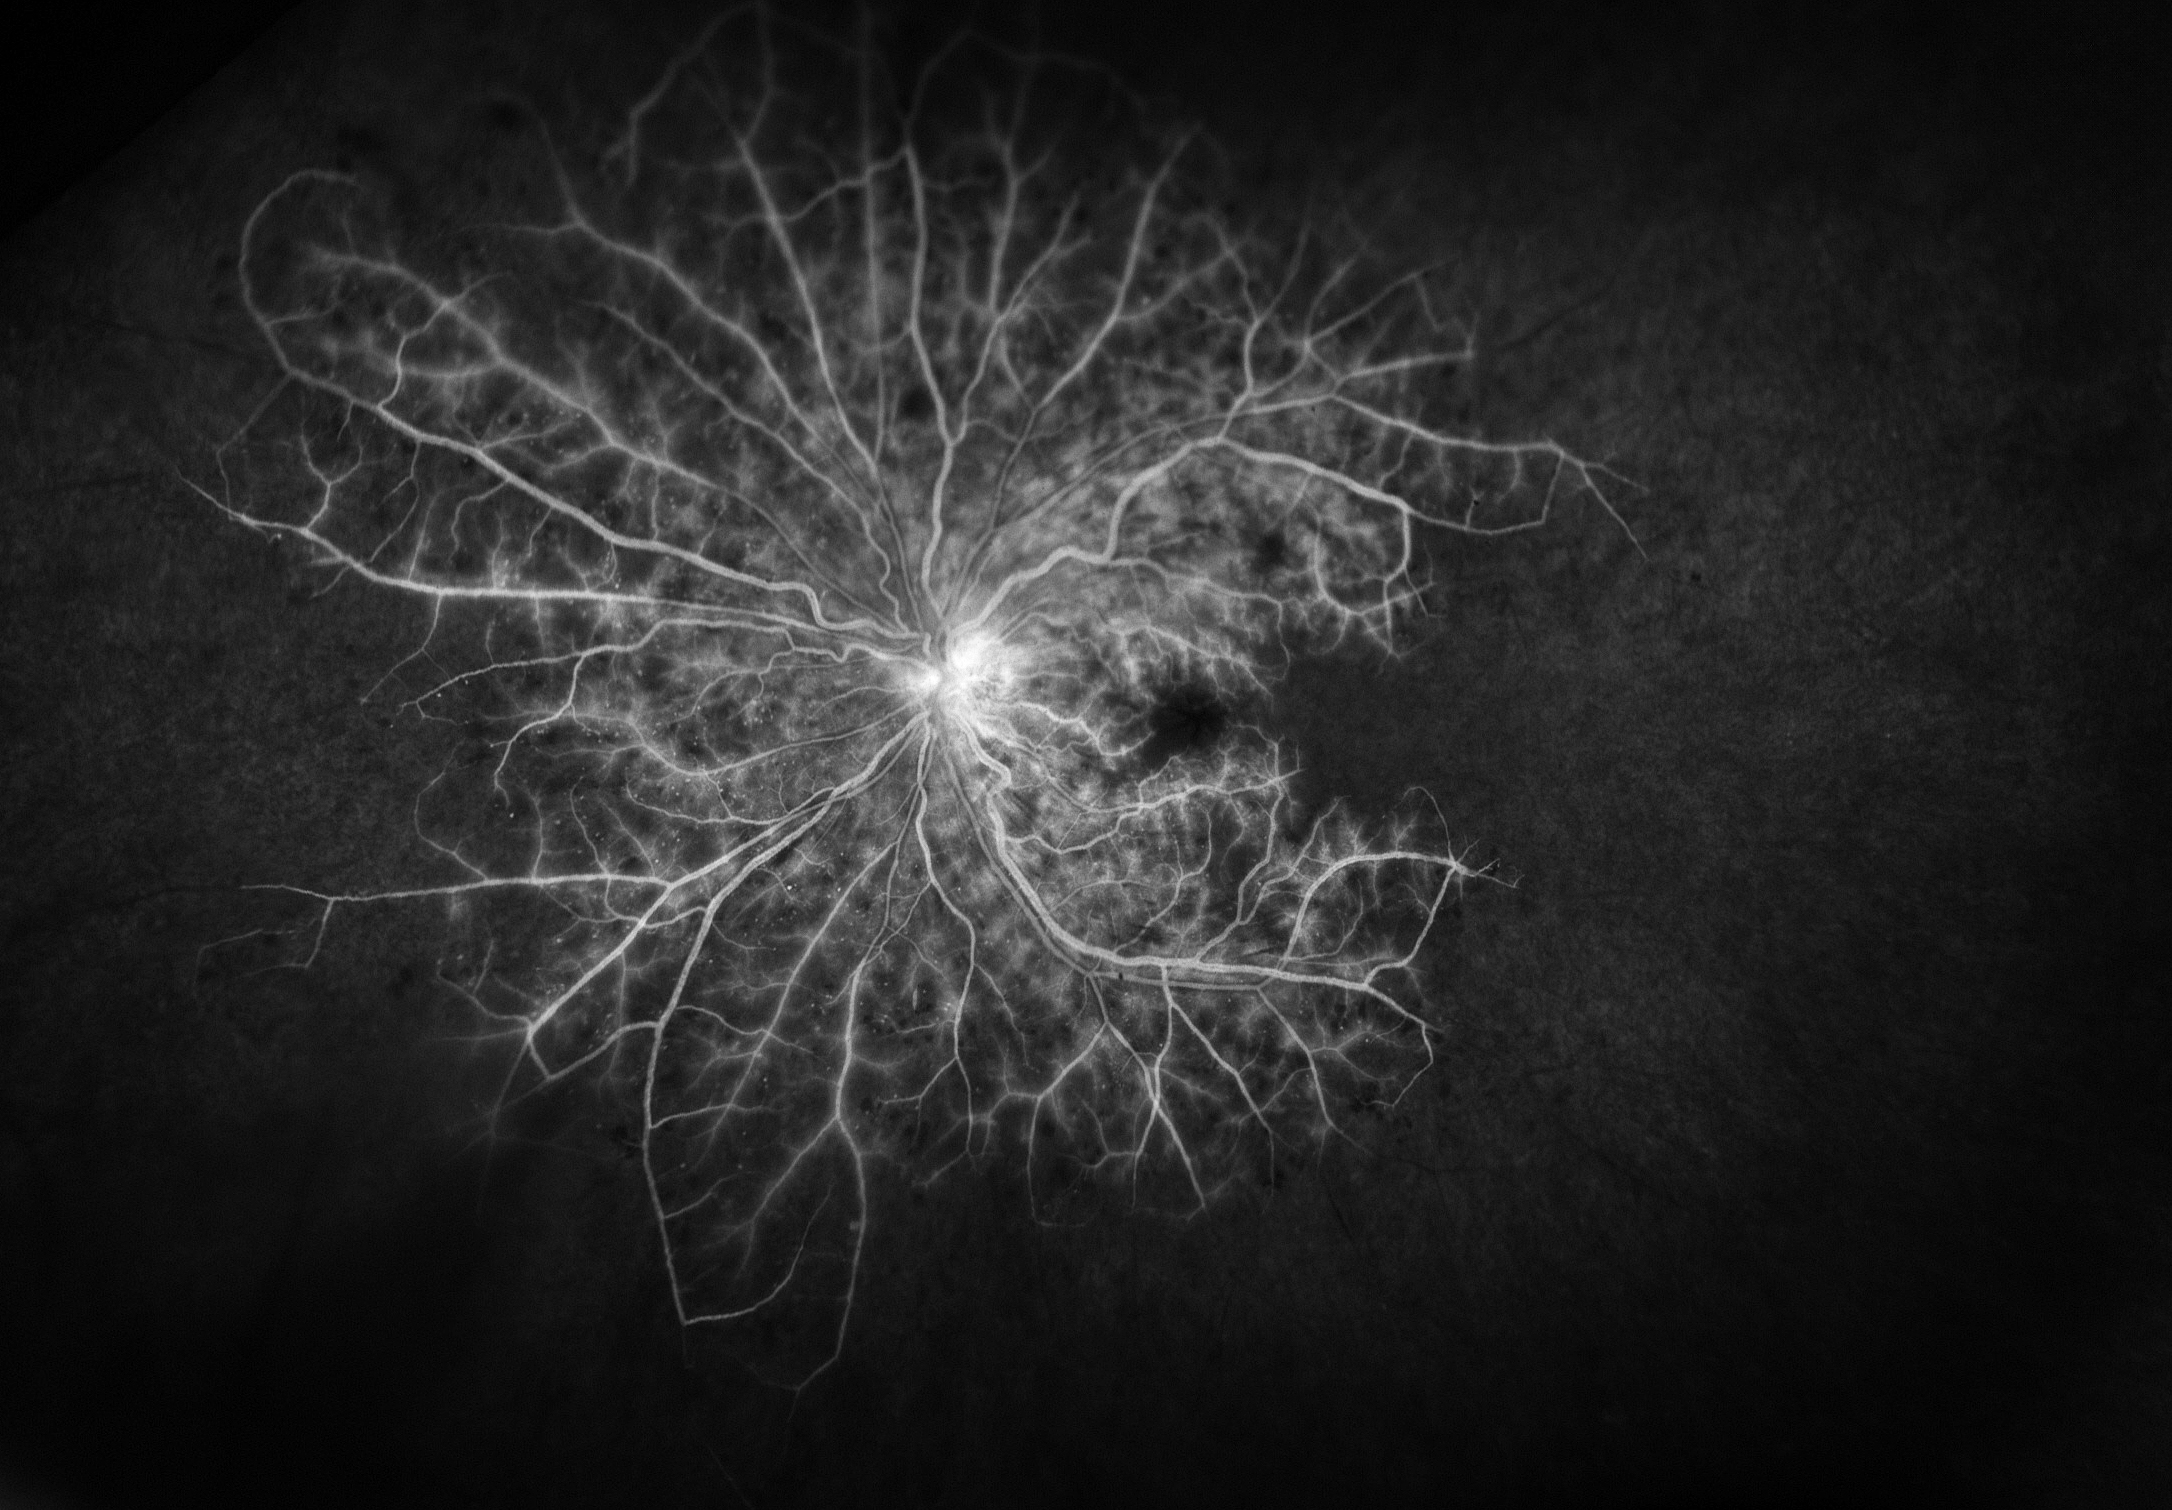

Vascularization Presented by Ben Serar This photograph received Second Place, Fluorescein Angiography (UWF) in the 2025 OPS Scientific Exhibit. Filed Under Cornea OPS Photo